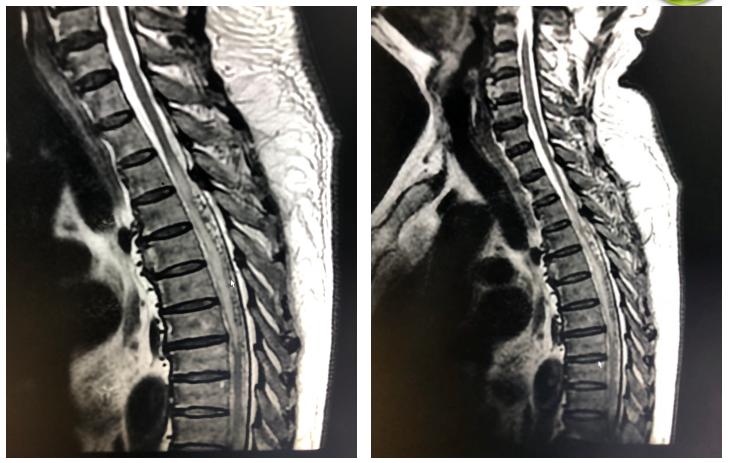

图3 传说中的“白萝卜与黑芝麻”

图4 患者的脊髓MRI

该患者脊髓磁共振(图4)显示胸段脊髓增粗,T1WI等信号、T2WI高信号(脊髓水肿、增粗即“白萝卜”),胸段蛛网膜下腔内长约10cm段密集点状、串珠状血管流空影(异常迂曲的静脉即“黑芝麻”)。

揉揉眼睛定睛再看,还真是传说中的“白萝卜、黑芝麻”来到了眼前!